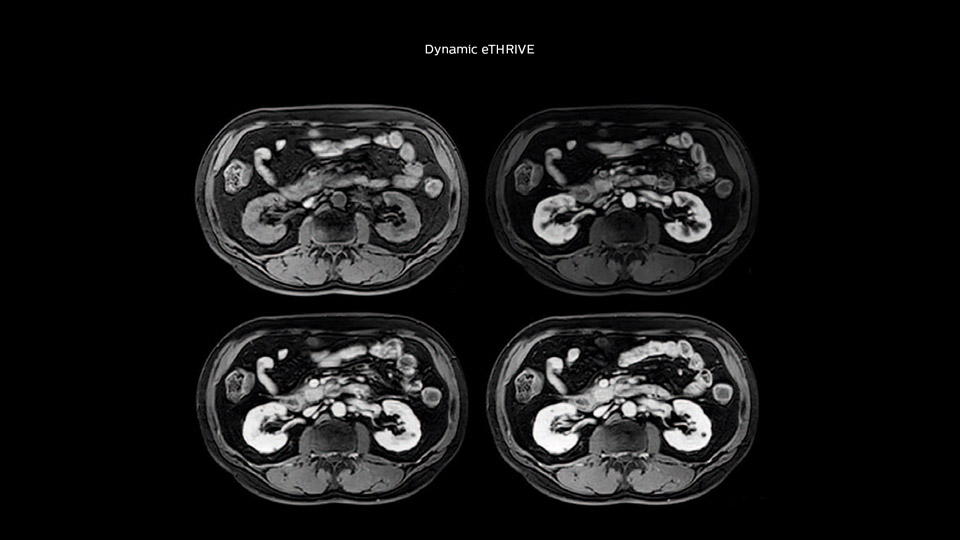

Comparison of liver MRI with and without MultiVane XD motion correction

In this example the image quality of the MultiVane XD images is evidently better than in the images without MultiVane XD. Ingenia 1.5T with dS Torso coil solution.

“We include mDIXON for the dynamic sequences because of the robust and homogeneous fat suppression we get with that. We had been using eTHRIVE, but we are now quite happy with mDIXON. Sometimes we use a medication to calm the bowels, to further improve the image quality.”